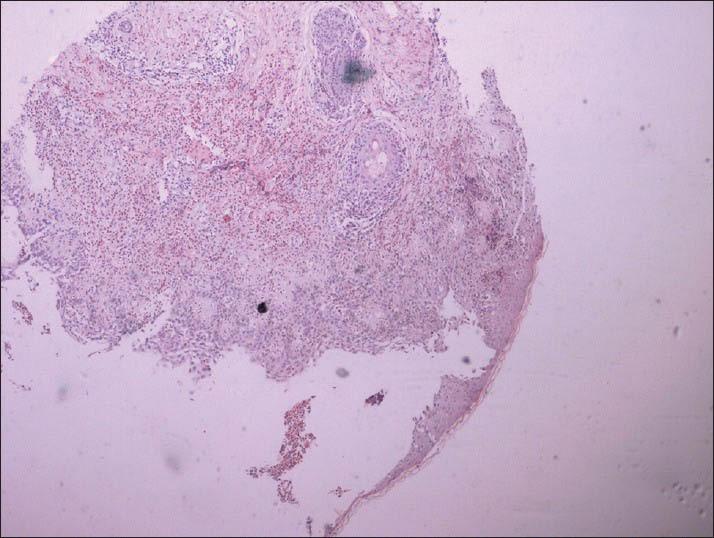

Pemphigus vegetans is a rare variant of pemphigus vulgaris. A 62-year-old woman presented with erythematous moist vegetative plaque on the left breast and left groin. There was no mucosal involvement. Histopathological and direct immunofluorescence findings were suggestive of pemphigus vegetans. She showed excellent response to oral steroids. Literature is scarcely available on the limited involvement with pemphigus vegetans without mucosal involvement.